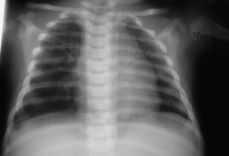

Figura 2.Resonancia magnética intraútero, T1 coronal: masa hipointensa en base pulmonar izquierda (flecha).

La exploración de RM se efectuó mediante un imán 1 Tesla (Siemens), utilizando la bobina principal de cuerpo como transmisora y receptora. Las series empleadas fueron axial y coronal SE potenciada en T1 TR/TE 600/15 ms, Axial TSE potenciada en Densidad Protónica y T2 TR/TE 4000/19/93 ms y una serie axial con técnica de inversión recuperación TIR TR/TE 2.300/19 ms TI = 140 ms. FOV = 350 mm, matriz = 192 x 256, grosor de corte = 5 mm.

Este estudio de RM, confirmó la presencia de una masa localizada supradiafragmáticamente en la base del hemitórax izquierdo, situada anterior a la aorta y a la izquierda de la cava. Se trataba de una masa hipointensa en las series potenciadas en T1 e hiperintensa en la serie TSE potenciada en T2 y en la serie TIR, con una intensidad de señal intermedia en Densidad Protónica. No se objetivaron en el seno de la masa o en relación a ella imágenes de vacío de señal que sugirieran la presencia de estructuras vasculares y tampoco se objetivó alteración en la integridad del diafragma ni anomalías cardíacas, pulmonares o abdominales asociadas.